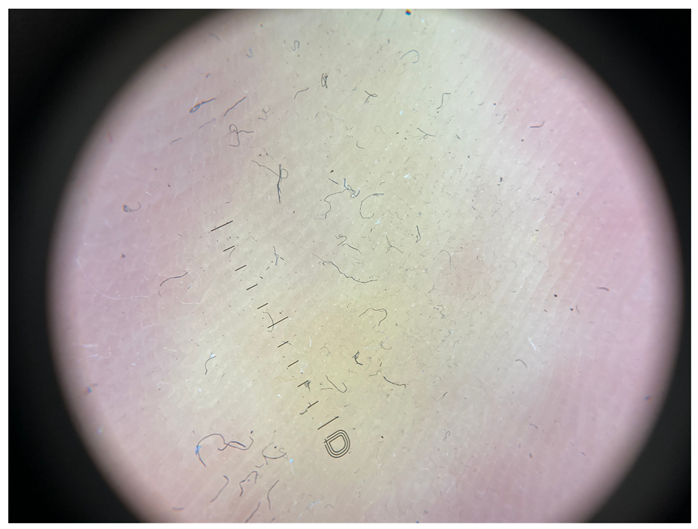

| Grade I | Foto Finder dermatoscopy, cross-polarization |

![]() | |

| DL-5 dermatoscopy, cross-polarization | |

| DL-5 dermatoscopy, parallel polarization | |